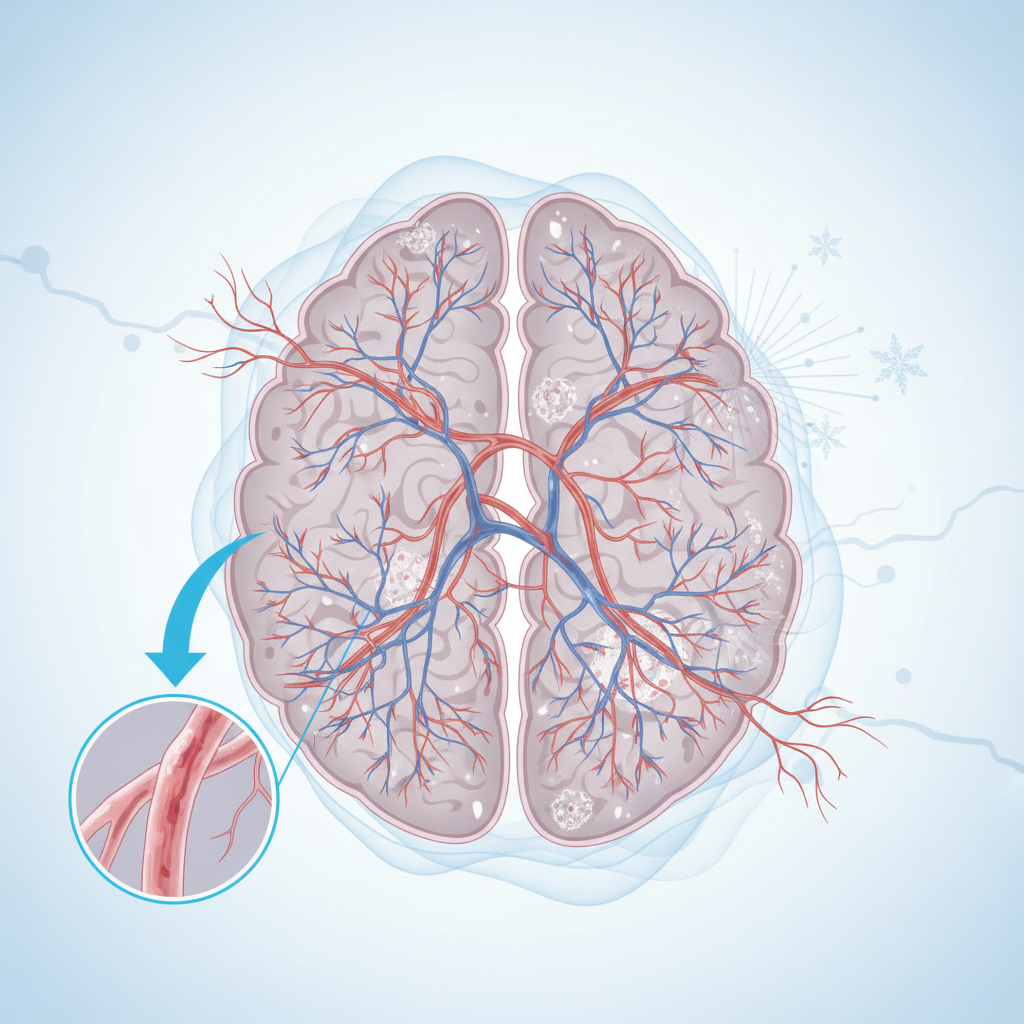

Фактори ризику, на які ми можемо впливати

Є чинники, що створюють постійний тиск на стінки судин і прискорюють їх зношення. Контроль цих факторів зменшує пошкодження і ризик ускладнень.

- Артеріальна гіпертензія. Підвищений тиск «б’є» по дрібних артеріях, робить їх жорсткими та ламкими. Коливання тиску теж небезпечні.

- Цукровий діабет. Надлишок глюкози ушкоджує ендотелій — внутрішній шар судин, погіршує контроль тонусу і живлення тканин.

- Паління. Токсини спричиняють запалення судин і підсилюють атеросклероз.

- Порушення ліпідного обміну. Підвищений холестерин і тригліцериди зменшують еластичність судин.

- Ожиріння та метаболічний синдром. Вони посилюють резистентність до інсуліну, підвищують артеріальний тиск і запалення.

- Апное сну. Повторні зупинки дихання знижують насичення крові киснем і перевантажують судини.